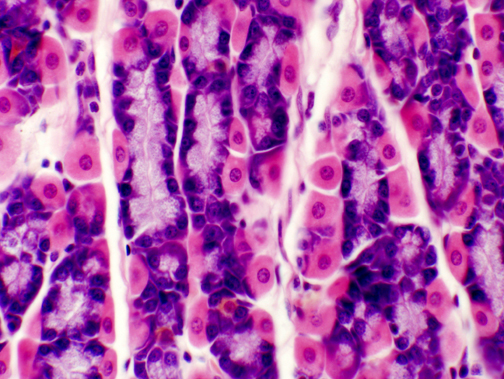

In this image the darkly stained cells are the chief cells. Chunky and angular in shape, and in H&E preparations very strongly basophilic, these cells have the typical 'secretory" appearance. In the electron microscope they show large amounts of RER and large numbers of secretory vesicles.

The parietal cells are by contrast very eosinophilic in their staining response. and stand out against the background of the chief cells quite well. Their shape is different too: instead of being angular they tend to be rounded.

The differences in staining and in shape are related to their functions. While the the chief cells show the typical properties of protein secreting cells, the parietal cells are essentially ion pumps. They have no protein secretion function and hence little RNA in their cytoplasm.

The parietal cells make hydrochloric

acid, to keep the pH of stomach juice low (about 2.0 to 3.0 is typical). This

pH is necessary to activate the

gastric enzymes. The role of the parietal cell

is to pump hydrogen ions out into the lumen of the stomach. It accomplishes

this task by extensive infolding of its apical surface and an enormous number

of mitochondria. The mitochondria inside the parietal cell can force hydrogen

ions across the membranes using active transport; this creates a sharp

concentration gradient between the surface channels and the open lumen of the

gland. The localized concentration gets so high that the ions diffuse out into

the lumen of the gland and eventually into the stomach.

Parietal cells are often binucleated: and in this image you can see a tri-nucleated one. The role of the parietal cell is to pump hydrogen ions out into the lumen of the stomach, thus acidifying the contents. It is able to do so by virtue of having enormous numbers of mitochondria (to provide the energy needed for active ion transport), and a system of extensive apical invaginations into which the ions are passed, creating localized concentration gradients that favor diffusion into the lumen. In the image at left, the "granularity" of the cytoplasm reflects both these features.

The chief cell is not nearly so dramatic in appearance, though it's equally important. Chief cells are shoved in among the parietal cells in groups of two or three. The enzymes produced by the chief cells are released in an inactive form; the acidic environment of the stomach hydrolyzes a fragment from the precursors, converting them to active enzymes.